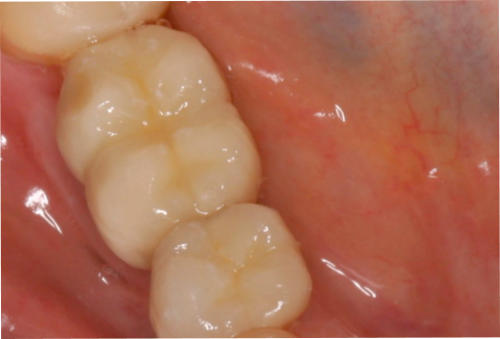

2. Transplantate für Zahnfleisch und Bindegewebe:

Durch Transplantate kann verlorenes Gewebe wieder aufgebaut werden. Damit wird eine dauerhafte Stabilität der Gewebe und damit auch des Knochens erzielt und eine gute Putzfähigkeit für Zähne oder Implantate erreicht. Beispiele: